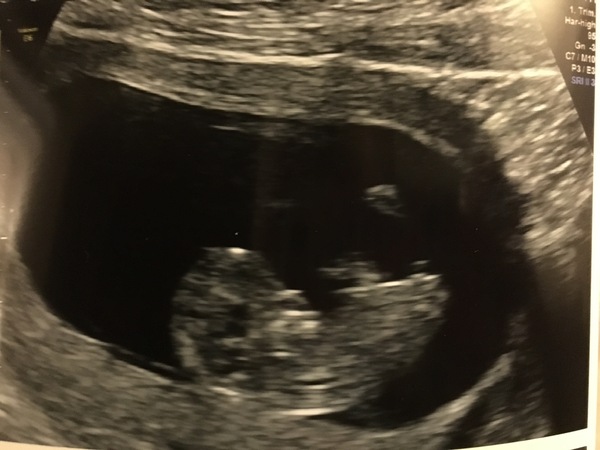

oliversmummy26 · 20/02/2017 13:30

In the meantime, I am feeling positive today I think that this little bean is a fighter and is hanging on in there...so here's our pic from yesterday...anyone any good with the nub theory? I want to say girl, but not sure if that's because we'd rather like a girl, we'd have one of each thenSmile

jpeg28 · 20/02/2017 16:57

oliver that's a lovely scan pic! I'm useless with the nub theory... Bec was spot on with mine though!!